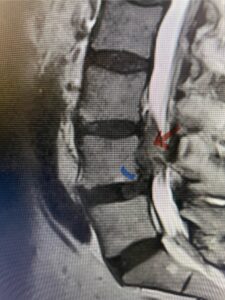

This 54-year-old morbidly obese female presents with progressive back and leg pain and quadriceps weakness. She had no diabetes. She failed all means of conservative management including physical therapy and epidural injections. On imaging she had severe stenosis at L3-4 with a disc protrusion and a slight grade 1 spondylolisthesis at L3-4 (Fig 1). We performed dynamic lumbar x-rays which demonstrated instability at L3-4 and L4-5 (Fig 2). The patient wished to have surgery. We performed an L2-4 decompressive laminectomy and L3-5 in situ fusion because of her instability. Post operatively the patient had relief of leg pain, although the patient was slow to mobilize.

Figs. 1a: Sagittal lumbar T2-weighted MRI demonstrating severe lumbar stenosis with a slight grade 1 at L3-4 and a disc protrusion (red arrow )